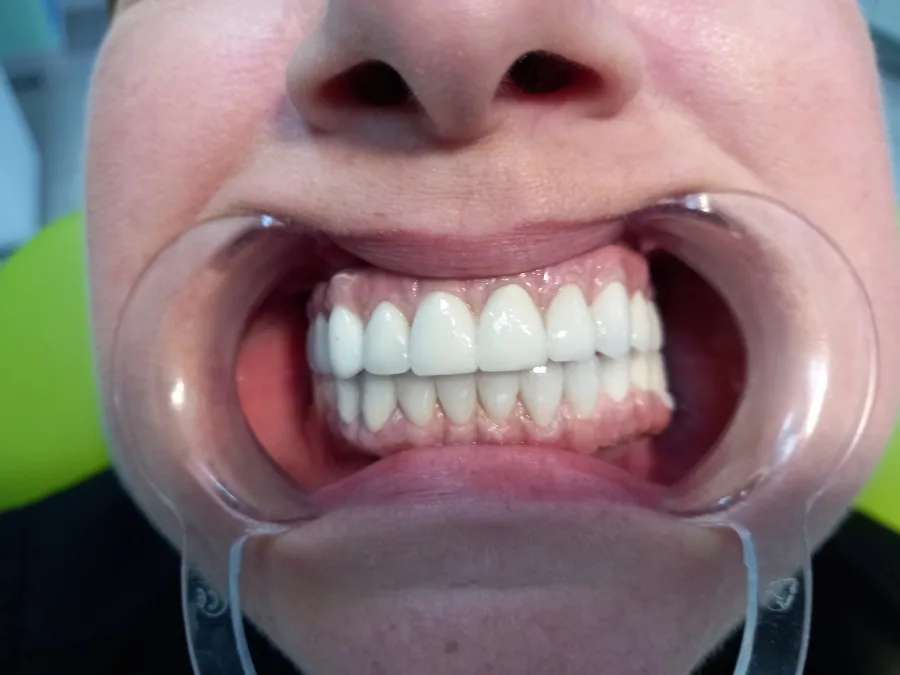

1. Prirodan Izgled i Osjećaj: Dentalni implantati pružaju prirodan izgled i osjećaj, integrirajući se s okolnim zubima i čeljusti.

4. *Fiksacija Krovnog Materiaja:* Nakon integracije, postavlja se kruna, most ili proteza, prilagođena individualnim potrebama pacijenta.